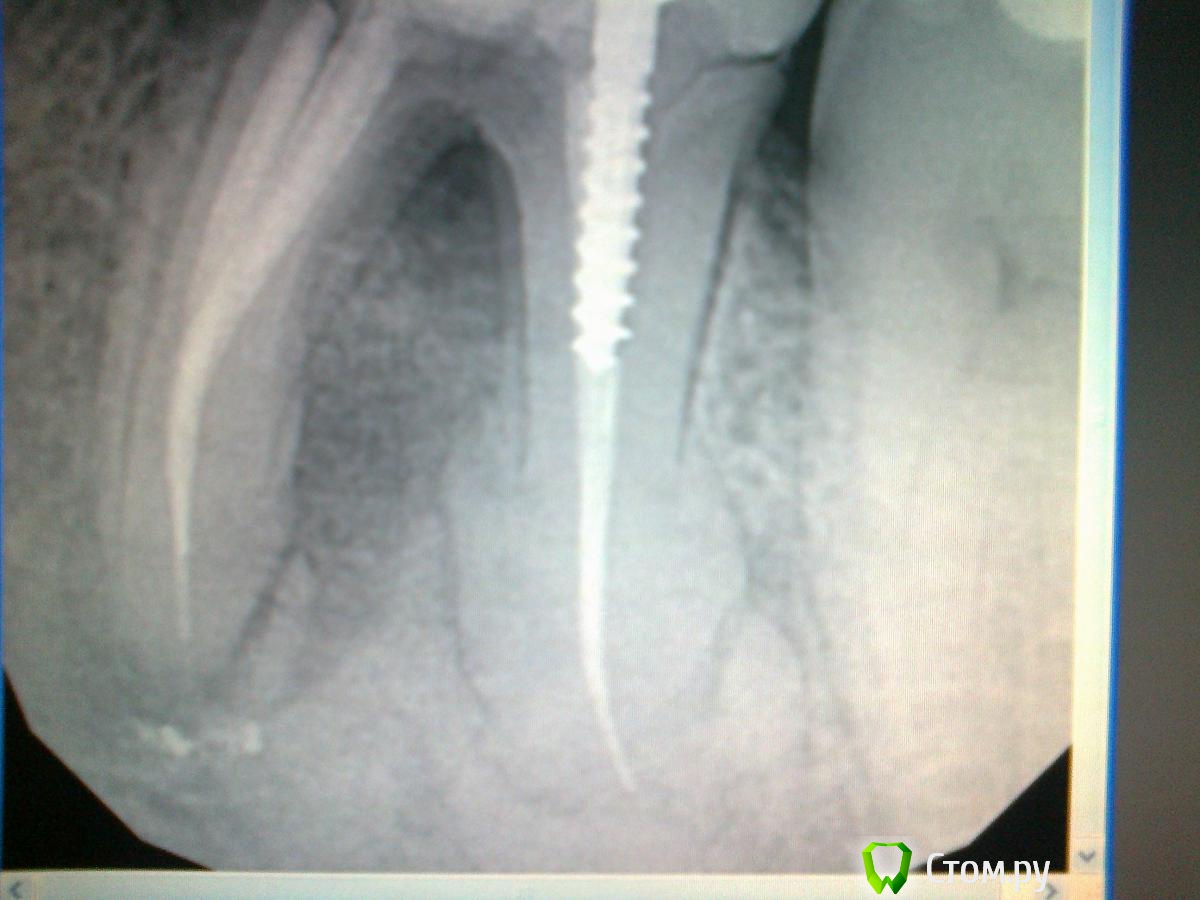

Acidrocker Опубликовано 28 ноября, 2013 Поделиться Опубликовано 28 ноября, 2013 Доброго дня. Не самая мировая проблема, но помогите, пожалуйста, советом. Ситуация такова:В 2008г. нижняя шестерка была пролечена по поводу периодонтита.Вот снимок от 2013г.Терапевт направил на удаление. Виден рост образования и, кмк, замещение им тканей корня, имеет капсулу.Что это может быть? Цементома, гиперцементоз? Как посоветуете поступить? Свои мысли - удалять как обычно и постараться "крестальным" доступом все убрать, при необходимости воспользовавшись борами. Ссылка на комментарий

Чертков Александр Опубликовано 28 ноября, 2013 Поделиться Опубликовано 28 ноября, 2013 Цементома, гиперцементоз Скорей всего... удалять как обычно и постараться "крестальным" доступом все убрать, при необходимости воспользовавшись борами. Так же думаю. 1 Ссылка на комментарий

Yurij.k Опубликовано 19 декабря, 2013 Поделиться Опубликовано 19 декабря, 2013 Гиперцементоз , как последствие защитной реакции организма на хр. воспаление . Ссылка на комментарий

Alexey Doc Опубликовано 20 декабря, 2013 Поделиться Опубликовано 20 декабря, 2013 Скорее всего нужно будет корень во всю длину минимум на 2 части разделить. Ссылка на комментарий